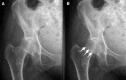

Radiologists rely principally on visual inspection to detect, describe, and classify findings in medical images. As most interpretive errors in radiology are perceptual in nature, understanding the path to radiologic expertise during image analysis is essential to educate future generations of radiologists. We review the perceptual tasks and challenges in radiologic diagnosis, discuss models of radiologic image perception, consider the application of perceptual learning methods in medical training, and suggest a new approach to understanding perceptional expertise. Specific principled enhancements to educational practices in radiology promise to deepen perceptual expertise among radiologists with the goal of improving training and reducing medical error.